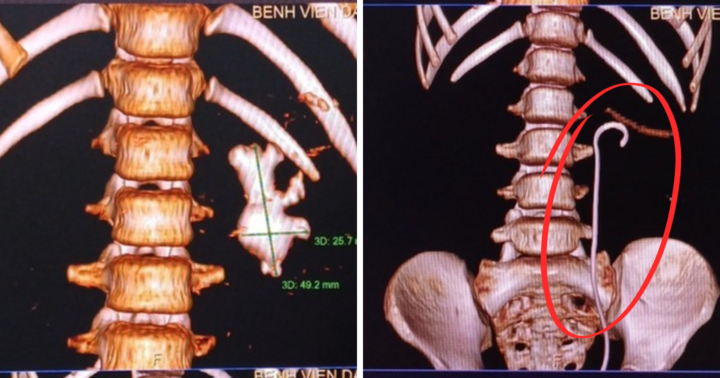

Kết quả chụp cắt lớp vi tính (CT) cho thấy trong bể thận trái của anh T. có rất nhiều sỏi đủ kích thước. Ngoài ra, nồng độ bạch cầu trong nước tiểu tăng là dấu hiệu nhiễm khuẩn đường tiểu nhưng người bệnh chưa có biểu hiện sốt, rét run.

Anh T. có tiền sử mổ ruột thừa, tán sỏi thận và niệu quản (ống dẫn nước tiểu từ thận xuống bàng quang) bên phải. Người bệnh mong lần mổ này sẽ xử lý sạch sỏi. Tuy nhiên, số lượng sỏi quá lớn, khó lấy hết trong một lần với các phương pháp tán sỏi nội soi thông thường. Mổ mở là giải pháp phù hợp nhất.

Sau 150 phút, ê kíp mổ lấy hết sỏi trong thận trái người bệnh. Theo quan sát, viên sỏi lớn nhất là sỏi san hô có nhiều nhánh, kích thước 5cm (cỡ quả trứng gà). Khoảng 5-6 viên sỏi kích thước khoảng 1cm và hàng trăm viên sỏi nhỏ hơn với đủ kích thước, hình dạng.